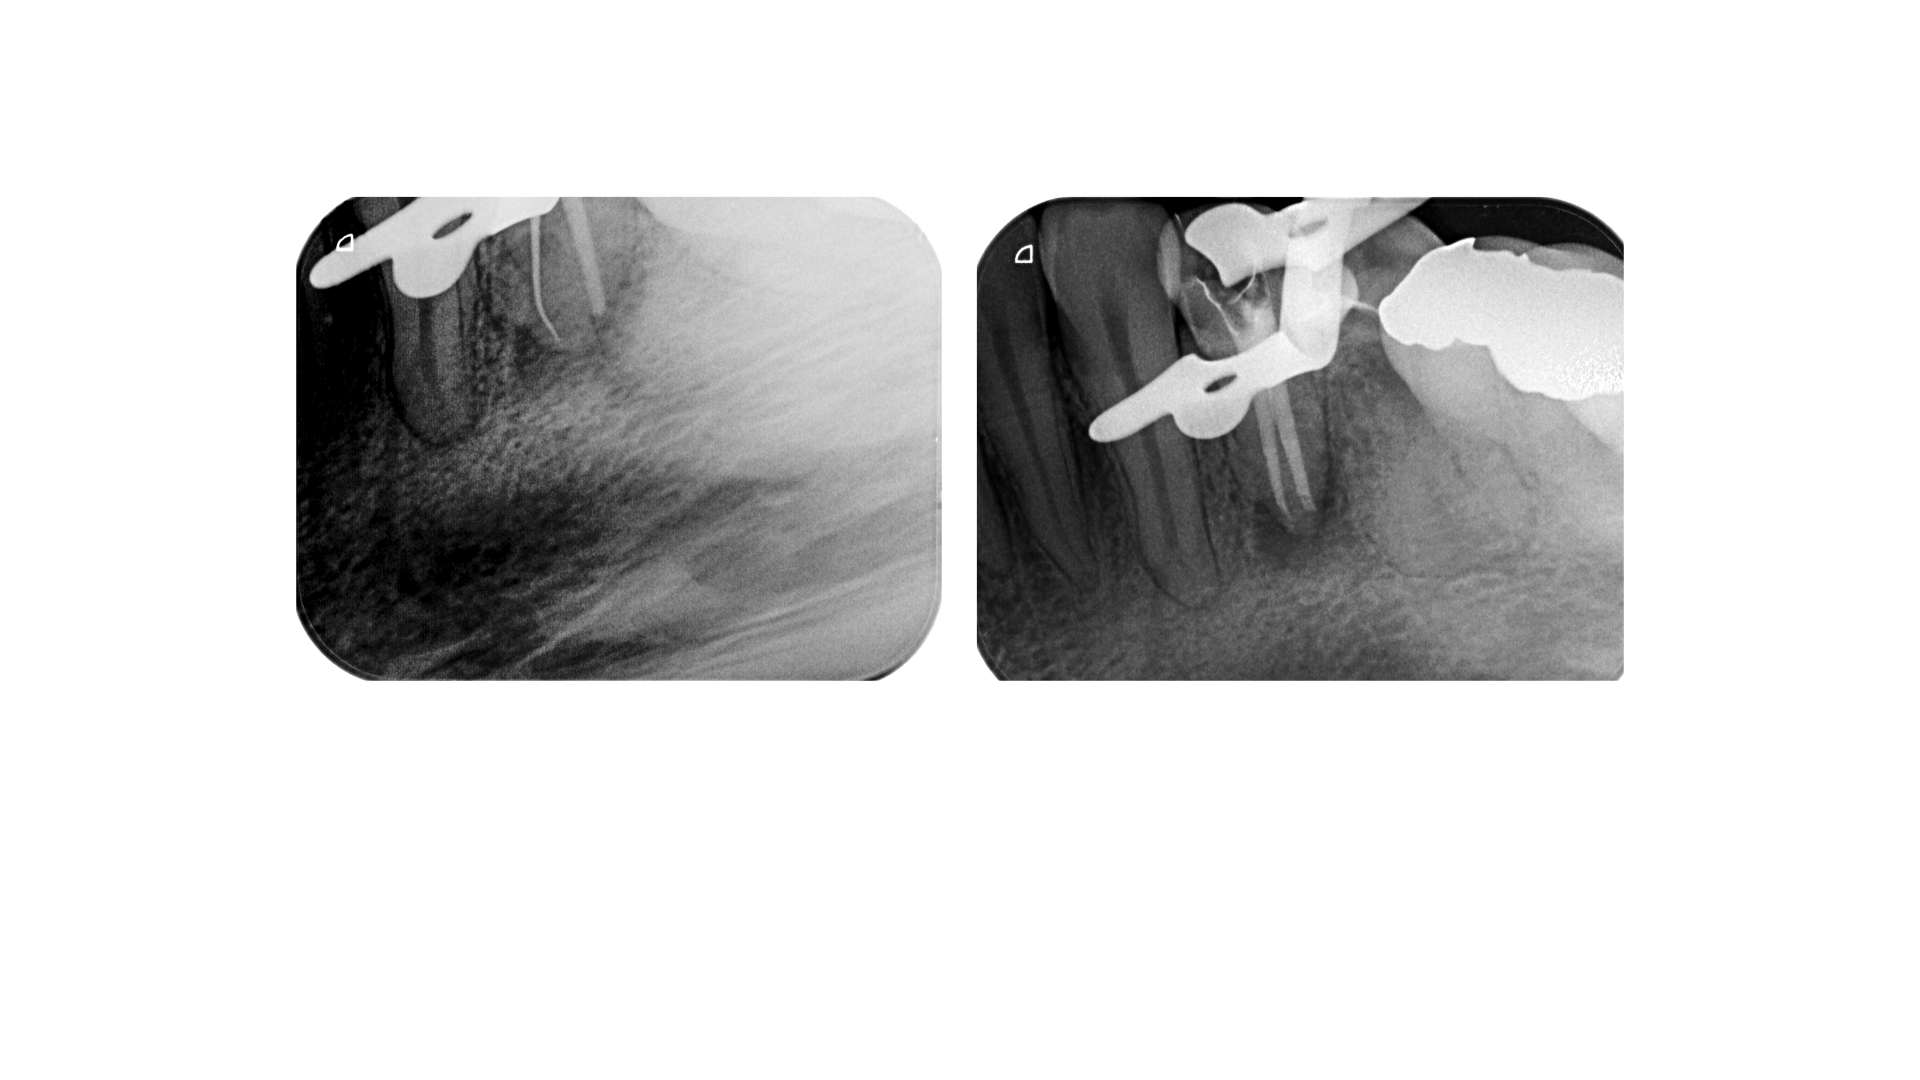

Routine UK -Prämolar ?